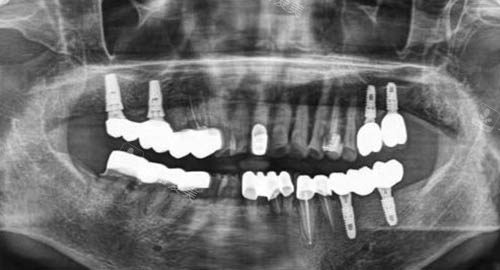

多颗牙齿种植ct